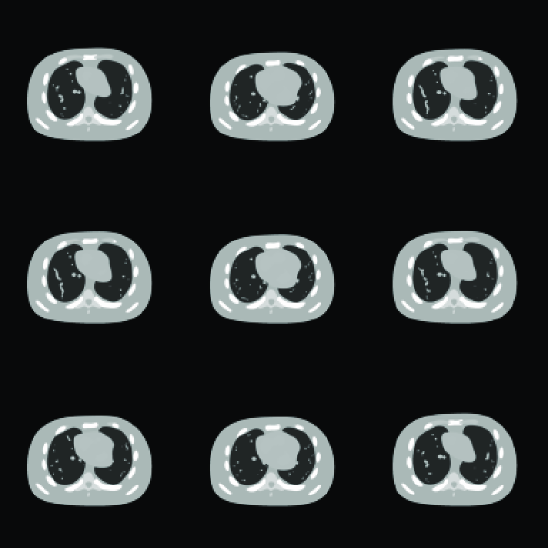

Comparing the restored images in Figure 3 with the corresponding ground truth images in Figure 1, it is found that our algorithm is able to capture the motions of the anatomy and restore the structures, even those small ones inside the lung. Meanwhile, observable artifacts inside the heart and at its boundary also exist. Quantitatively, the relative error of the restored cine-CBCT images is 3.97%percent3.973.97\%.

To further look into the reconstruction results, we plot the columns of 𝑳𝑳\bm{L} in Figure 4(a), where each column is reshaped into a 128×128128128128\times 128 image. These images form the basis to represent all the reconstructed cine-CBCT images. It is observed that the first one is similar to an image averaged over all the cine-CBCT images. Its presence provides an overall structure that is common to all the images in the cine-CBCT. Meanwhile, other basis images represent differences between images of 𝑼𝑼\bm{U}. We also plot the corresponding coefficients in 𝑹𝑹\bm{R} in Figure 4(b), which attain a periodically variation pattern, indicating the patient respiratory motion.

Refer to caption

Figure 3: The restored cine-CBCT image from noiseless data. The relative error is 3.97%percent3.973.97\%. From left to right, top to bottom: frame 40,80,,360408036040,80,\ldots,360.